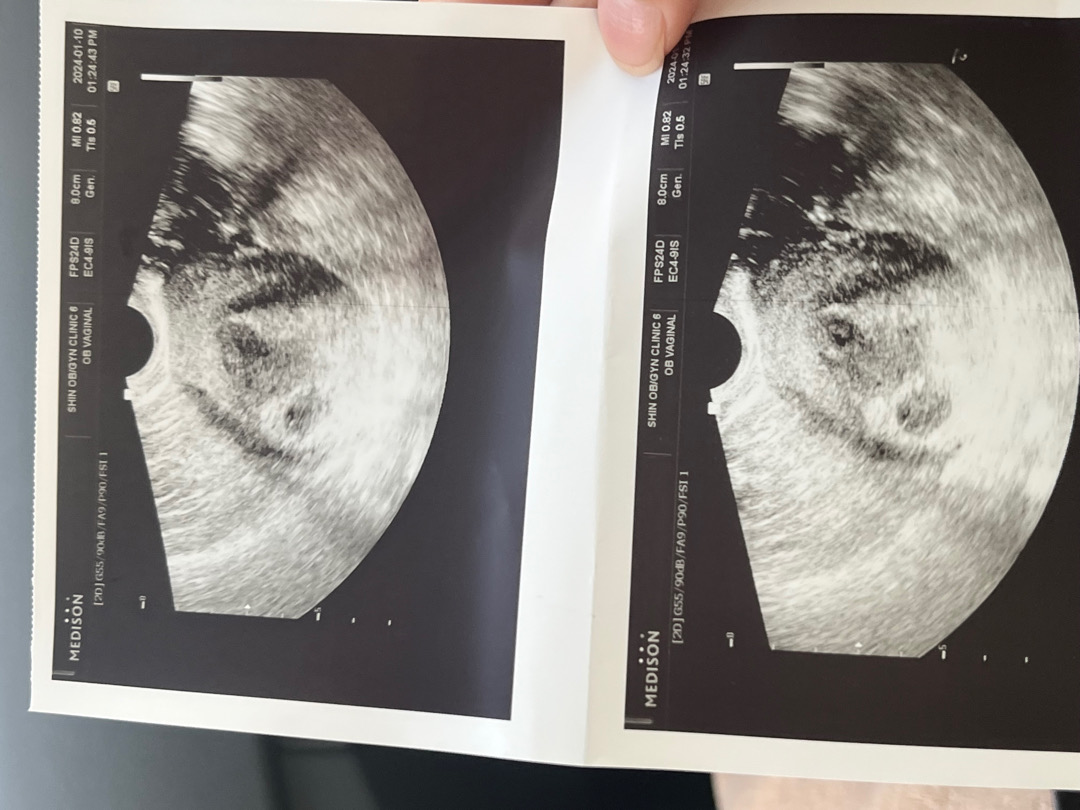

5주4일 초음파

오늘 드디어 일주일만에 방문후 초음파 보고왔어요 화면으로 난황까지 잘 있는거 봤는데요 프린해주신 초음파 사진에는 안나타나고 이렇게 화질 안좋은게 맞나요….? ㅋㅋㅋㅋㅋㅋㅋㅋㅋㅋ거의 뿌연대ㅐㅐ 초음파 기계차이인지 다른분들 초음파 궁굼합니다ㅠ

아기집이 두개로 보여서요 ㅎㅎㅎㅎㅎ

초반에 치검수치 높아서 원장님이 계속 둥이 언급 하셨는데 이번에 별말 없으시더라고요! 단태아 인거같아요 ㅎㅎ 휴~~~

혹시 5주4인데 크기가 8cm인가용..?

아니요! 저기위에 8이라나온건 아닌거같아요ㅠㅠ 잘 있다고만 듣고 cm 은 못들었어요ㅠ